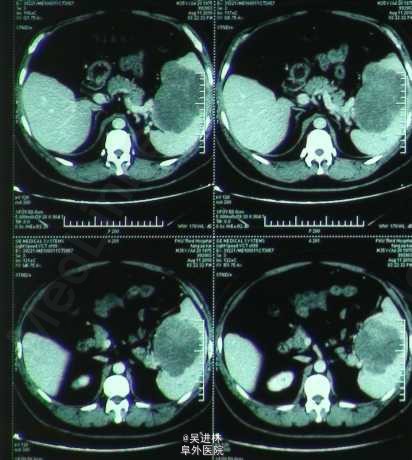

患者男,40岁,常规体检发现脾脏占位入院。主诉无特殊,无消化道症状,无贫;查体无特殊。CT表现:平扫为边界不清的低密度影,增强扫描各期均无强化。大体标本:脾脏腹侧可见一结节状肿块,周边红色,其内可见白色瘢痕。术后病理:脾淋巴管瘤。治疗:手术切脾。 拓展:淋巴管瘤可以发生在任何有淋巴管的地方,但是长在脾脏比较罕见。由于罕见,诊断困难。虽然它是良性病变,但是有病理性脾破裂的风险,最好切除,尤其是伴有临床症状的时候。